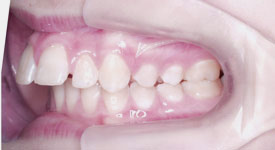

Crowding Front